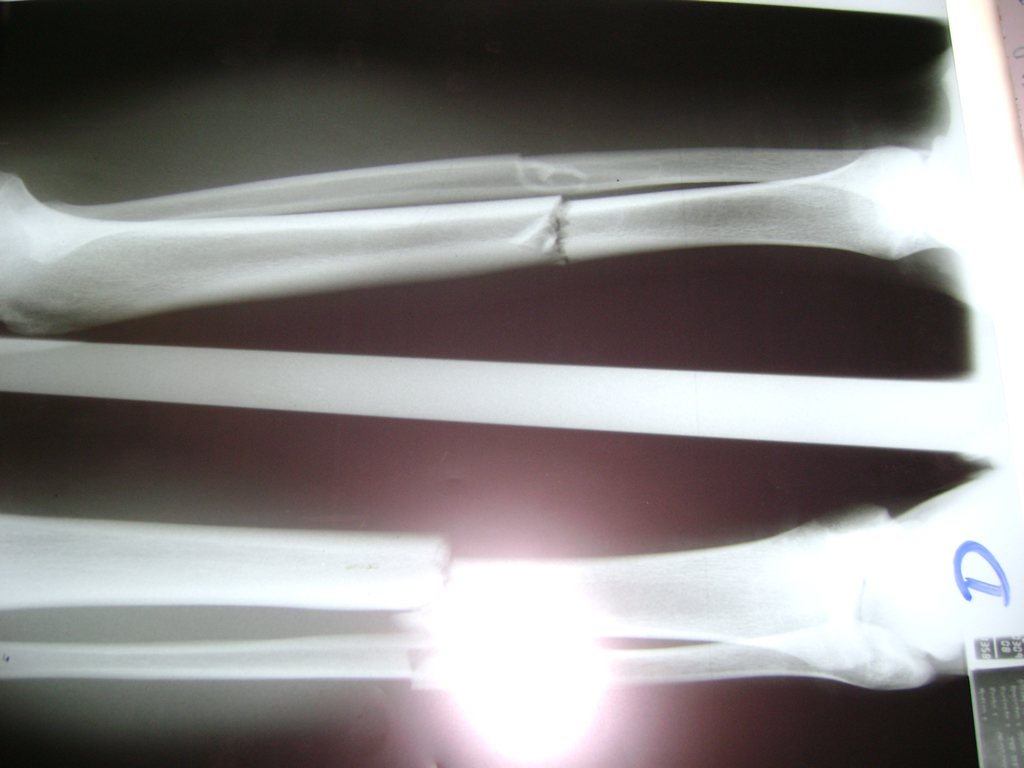

Aunque cada uno de estos huesos puede fracturarse por separado, normalmente la rotura es una lesión que se produce de forma conjunta

La mayor parte de las roturas implican a la parte proximal del hueso (parte del hueso próximo a la rodilla) o a la parte distal (parte del hueso cerca del tobillo).

Debido a la fina cobertura de piel que recubre la tibia y el peroné, las fracturas generalmente son abiertas, es decir, el hueso roto rasga la piel, atravesándola. Las fracturas de tibia y peroné generalmente se producen por un fuerte impacto o torsión.